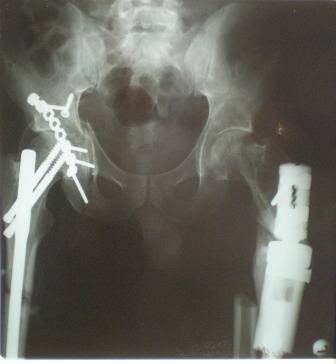

Глубокоуважаемые коллеги! Благодарю за полезные советы, которые нам очень помогли в выборе оперативной тактики пациента. 13.02.08 мы выполнили первый этап оперативного лечения этого больного. Вначале зафиксировали левое бедро АВФ Гофмана

(главный травматолог области достал из каких-то «анналов», первый раз в жизни увидел этот аппарат в живую). После наложения «ДРУ Челнокова» выполнили ЗИО правого бедра реконструктивным штифтом Chm. Далее уложили пациента на левый бок и выполнили остеосинтез вертлужной впадины. Ограничились задне-латеральным доступом без отсечения вертела, чтобы не утяжелять операцию. Результат прилагается.

Следующим этапом планируем выполнить ЗИО левого бедра.